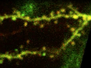

Cancers that spread to bones are often difficult to treat, but finding out how tumour and bone cells live side by side may help to heal osteolytic lesions – tears created in bone tissue as a tumour grows inside. Intravital microscopy watches as this lesion, in mouse bone, widens over several days. From blue to green to red – consecutive overlapping pictures show the fringe of the hole eaten away by bone resorption – when bone cells are broken down. This bone tissue was actually grown in a lab under a mouse’s skin, with a thin surface ideal for peering through. Treating the lesion with a chemical called zoledronic acid slows the bone’s deterioration – just as it does in human patients – but doesn’t stop the cancer growing. Using biological models like this, scientists can now test combinations of drugs that preserve the bone, while targeting the cancer cells inside.